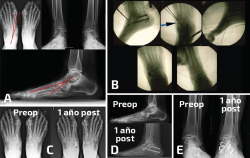

Figura 4. Paciente con consolidación viciosa de una doble artrodesis tarsiana que muestra excesivo valgo y un tobillo con una artropatía asimétrica y muy doloroso. A: el estudio radiológico muestra la deformidad en valgo y la transmisión de ese valgo a la tibiotalar; B: en las imágenes de radioscopia intraoperatoria se aprecia la realización de una osteotomía varizante de calcáneo y de una osteotomía de cierre talonavicular con una cuña de base medial y plantar; C: radiografías de ambos pies en carga en proyección dorsoplantar que muestran las diferencias en la alineación al año de la cirugía; D: misma situación en proyección lateral; E: radiografías de ambos tobillos en carga en proyección anteroposterior que muestran las diferencias en la asimetría al año de la cirugía. La paciente se encontraba asintomática de su dolor tibiotalar.